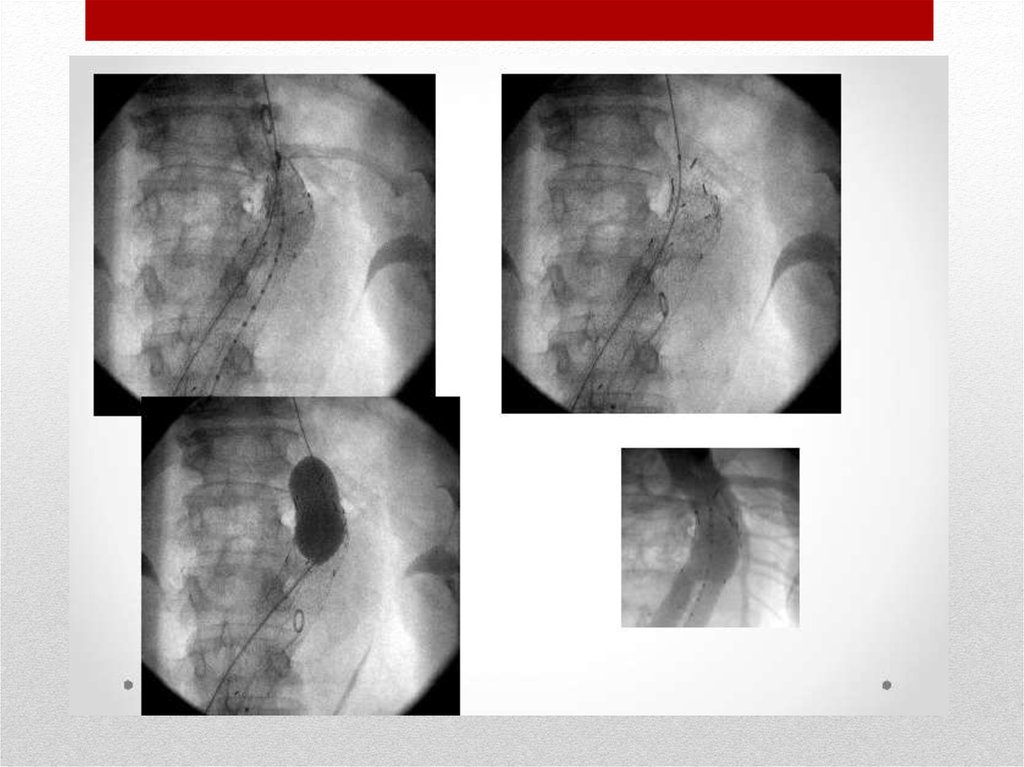

Эндоваскулярное стентирование

Стент вводится в сложенном положении через

небольшой разрез бедренной артерии при помощи

специального проводника и расплавляется в месте

расслоения, фиксируется внутри сосуда и выключает

аневризму из кровотока.